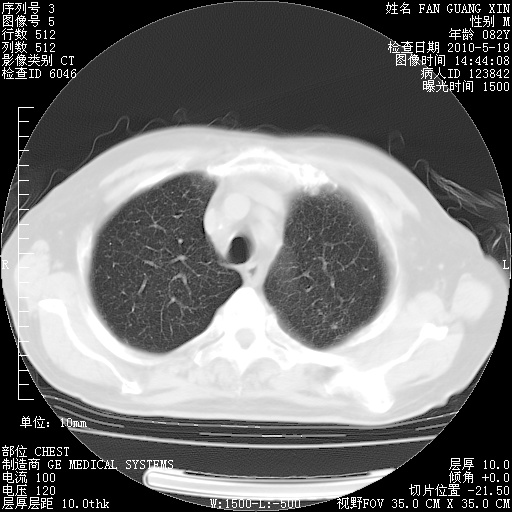

可改为口服强的松40-50mg/d治疗,若病情仍稳定,胸部阴影不再吸收可逐渐减量